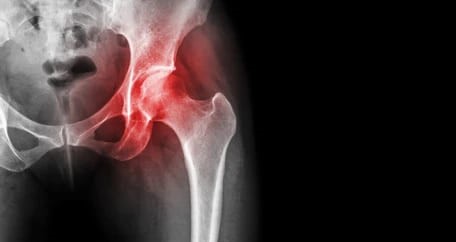

골반괴사는 골반 주위의 뼈가 혈액 공급을 충분히 받지 못해 괴사 하는 질병입니다. 이로 인해 뼈가 약화되고 통증이 동반됩니다. 이때 음식은 어떻게 골반괴사 예방과 치료에 도움이 될까요? 뼈 건강을 유지하는 데 필수적인 영양소를 음식으로 섭취함으로써 골반괴사를 예방하거나 증상을 완화할 수 있습니다. 칼슘, 비타민 D, 마그네슘 등 뼈 건강에 좋은 영양소를 충분히 섭취하는 것이 중요합니다. 이러한 영양소는 음식으로 쉽게 얻을 수 있어서 약에 의존하지 않고도 건강을 관리 수 있습니다.